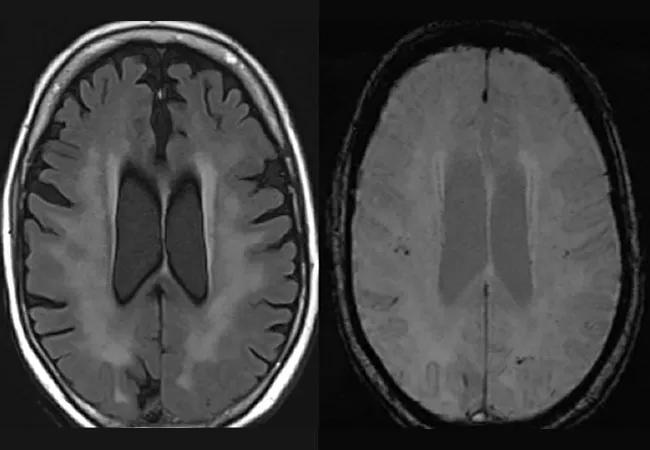

MRIs of the brains of two patients with COVID-19 ARDS demonstrating extensive white matter abnormalities (A, C) with underlying cerebral microbleeds (B, D).

In contrast to those similarities between groups, two unique patterns of injury were seen only in the COVID-19 patients: hemorrhagic leukoencephalitis (3 patients; 12%) and bilateral cerebral peduncular ischemia with microhemorrhage (2 patients; 8%).

After matching to control for age and sex, comparison of MRIs between ARDS patients with and without COVID-19 revealed a high frequency of cerebrovascular injury in both groups but no significant differences between groups in rates of cerebrovascular injury overall, cerebral ischemia, intracranial hemorrhage or cerebral microbleeds. Among the matched patients, cerebral microbleeds were seen in about half of patients in both groups (52% of those with COVID-19 and 41% of those without COVID-19). Ischemic injury was also common, seen in 35% of patients with COVID-19 and 43% of patients without COVID-19.

Dr. Shoskes adds that the hemorrhagic leukoencephalopathic imaging pattern observed exclusively in several of the patients with COVID-19 has been described in prior reports of patients with COVID-19 characterized by extensive white matter changes with underlying hemorrhage or small bleeds. “Further research into the mechanism of the diffuse white matter injury and hemorrhage in COVID/COVID-ARDS is necessary,” he concludes.